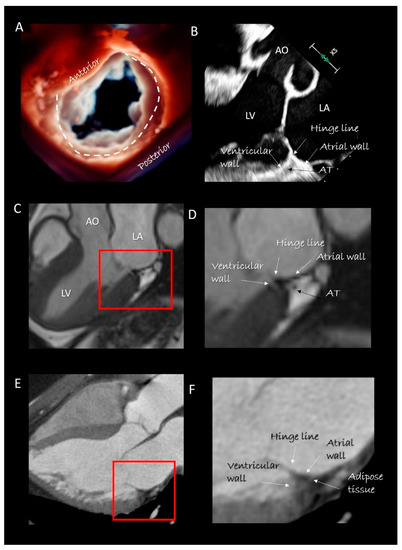

The posterior segment anchors the posterior leaflet and can be roughly depicted as a “C-shaped” structure covering the posterior aspect of the MA from the left to the right trigones. This segment is actually the result of the convergence of four structures: the atrial wall, the leaflet hinge line, the marginal free wall of left ventricle and adipose tissue (AT) (Figure 2). A thin fibrous string (which is actually the “true” posterior annulus) “glues” these components together. However, this fibrous string is discontinuous and in those parts in which it is absent, the posterior leaflet is inserted directly on the junction of ventricular and atrial myocardium [12]. The sphincteric-like contraction of the MA is facilitated by this anatomical arrangement. Indeed, those parts of the posterior hinge line directly attached on ventricular myocardium follow the contraction of LV reducing the MA area by 20–30% [13]. The smallest area occurs in isovolumetric contraction preparing an effective leaflet coaptation, while the largest area of MA is seen in the isovolumetric relaxation, anticipating the torrential early filling. Notably, in this “pre-systolic” phase, atrial contraction plays a fundamental role, confirming that the atrial myocardium is an integrant part of posterior MA [14].

Figure 2.

(A) 3D transesophageal echocardiography (TEE) still frame image of mitral valve forms an overhead perspective with a specific rendering algorithm that permits a movable source of light. With a source of light behind the valve, the two components of mitral annulus are well visible (the curved dotted line marks the posterior segment). (B) 2D TEE cross-section long-axis view showing the four components of posterior segment of annulus. The adipose tissue (AT) has a different texture compared with surrounding tissues. (C) CMR cross-section long-axis view. (D) Magnified image of the structures inside the red square in C showing the four components of posterior segment. The AT can be distinguished because the signal is much stronger (white in color) than that of surrounding structures. (E) Computed tomography (CT) cross-section long-axis view. (F) Magnified image of the structures inside the red square in E showing the four components of the posterior segment. As AT is more hypodense to x-ray, it appears as an area that is darker than the surrounding structures. AO = aorta; LV = left ventricle; LA = left atrium.

Imaging Techniques

Cross sections obtained by 2D TTE and TEE, CMR and CT perfectly portray these anatomical details (Figure 2). Three-dimensional TEE from an overhead perspective shows unique images of the entire hinge line of leaflets. Notably, in the cross section, the fibrous posterior annulus should appear as a fibrous nodule. It must be emphasized that none of the above-mentioned techniques is capable of visualizing this fibrous nodule as a distinct structure. Thus, the only means to visualize the posterior annulus is through histological specimens. The absence of a rigid “C-shaped” semi-annulus facilitates the sphincteric-like contraction. Those segments of posterior leaflet attached directly on ventricular myocardium freely follow contraction and relaxation of left ventricle (Figure 3). CMR shows that from the atrioventricular groove, the adipose tissue (AT) penetrates deeply up to the base of posterior leaflet. This “intrusiveness”, along with the fibrous skeleton of the heart, may contribute to the electrical insulation between the atrial and ventricular musculature and may provide a mechanical protection to coronary artery buffering and to the torsion induced by arterial pulse and myocardial contraction. Cross-sectional planes 2D/3D TEE, CT scan and CMR show as the hinge line of the anterior leaflet is more apically displaced than the hinge line of aortic leaflet. The space between the two hinge lines is occupied by the above-mentioned mitral–aortic curtain (Figure 4A,B). Three-dimensional TEE permits visualizing the mitral–aortic curtain from an “en face” perspective showing as the base of the AML, its hinge line, the mitral–aortic curtain and the ILT, which appear as a single area with no boundaries (Figure 4C,D).